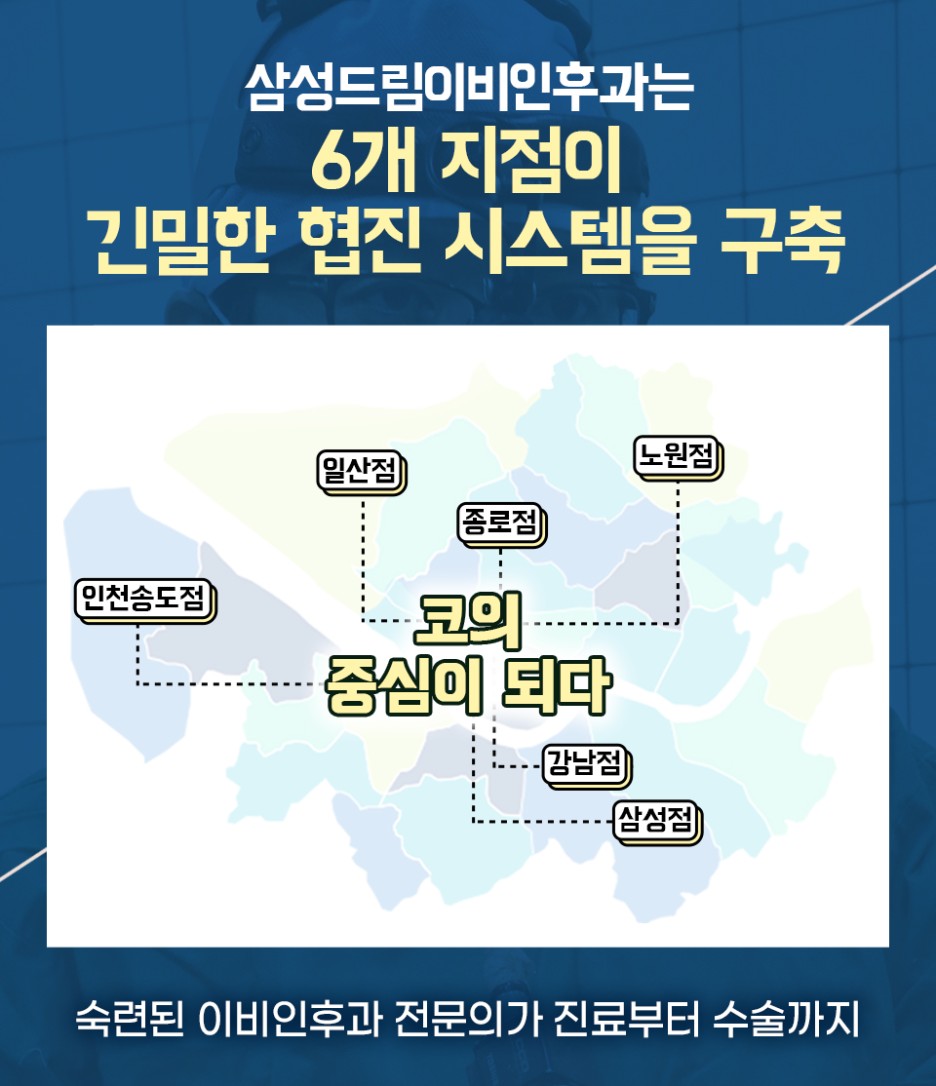

안녕하세요 삼성드림이비인후과 일산점 입니다. 여러 신체 부위에서 약간의 불편이 발생하면 심한 증상을 가지고 있는 경우라고 할 수 있습니다. 가장 흔한 부위를 말하며 코에 관한 내용이라고 할 수 있습니다. 코에는 다양한 질환이 있었습니다. 단순히 코에 관한 자극만 주는 것이 아니라 그 주변에도 영향을 받을 수 있었습니다.